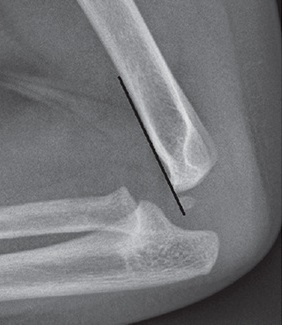

Pediatric Wrist Fracture Treatment in Raleigh,NC Understanding Pediatric Wrist Fractures Wrist fractures are the most common broken bones in children, accounting for approximately 280,000 emergency department visits each year in the United States. Most pediatric wrist fractures heal completely with proper treatment, allowing children to return to their normal activities without long-term problems. Types of…